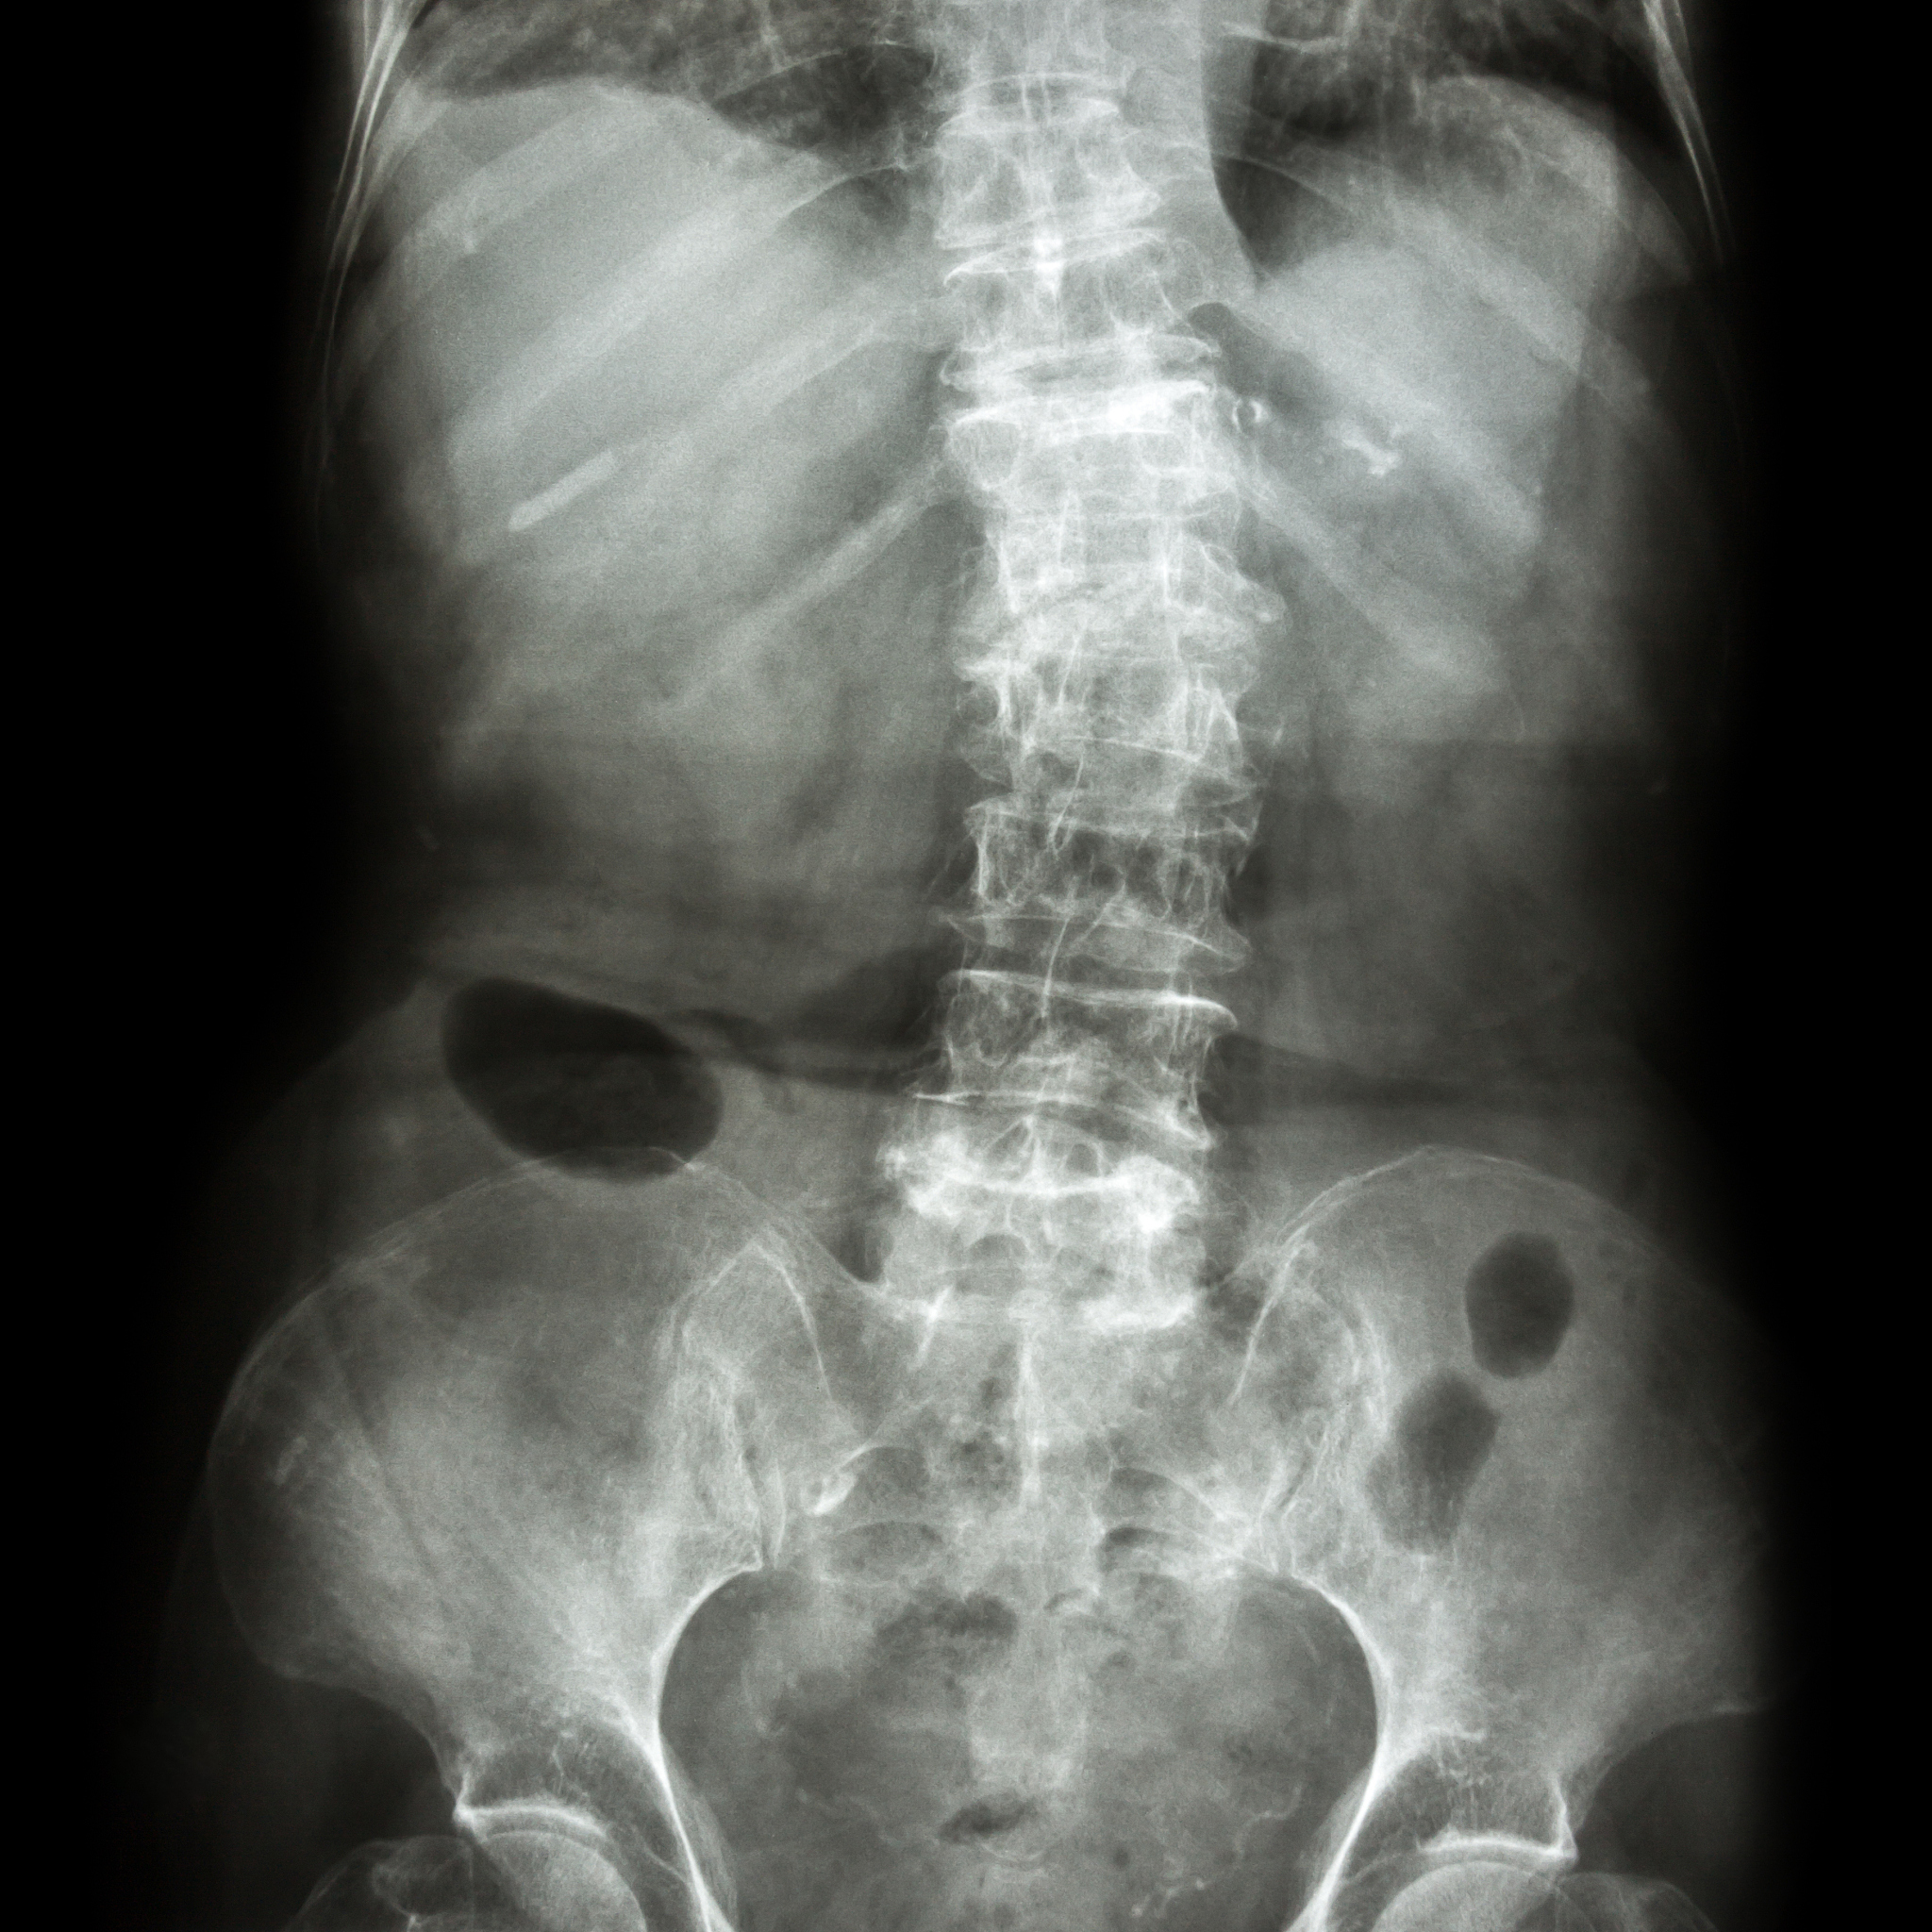

椎体成形术(PVP)是一种治疗骨质疏松症或脊椎骨折的手术方法,但并非适用于所有患者。以下是PVP的绝对禁忌症:

椎体成形术(PVP)绝对禁忌症:谁不适合做?